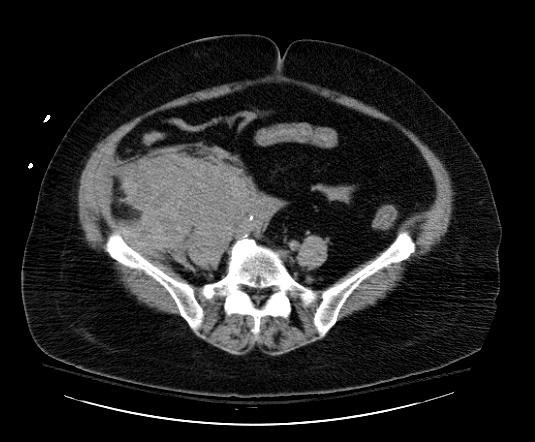

Забрюшинная флегмона: диагностика и лечение